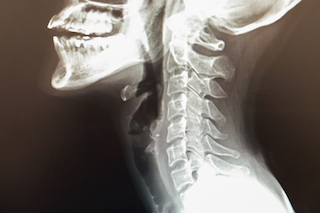

首の骨折はX 線検査で診断できます。首の骨折は脊髄の非常に高い位置にありますが、その骨折が脊髄にも損傷を与えると、下半身全体、つまり骨折箇所より下のすべてに影響を与える可能性があります。首の骨折による脊髄損傷は、次の方法で診断できます。